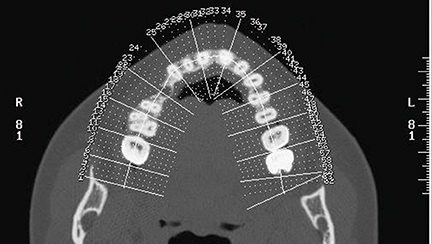

First- and second-level radiographic examinations (panoramic X-ray and CBCT) revealed a marked horizontal atrophy with a moderate vertical component (Figs. 2–3).

Fig. 2: CBCT cross sections

Block by Block

Fig. 3: CBCT axial view

Since this was a predominantly horizontal bone atrophy, the thickness of the edentulous ridge segment was recorded at a distance of 8 mm from the crest, both before and after the procedure.

By comparing the preoperative volumetric data with the measurements taken at the time of the second-stage surgery, a transverse gain was observed—from 3.5 mm (preoperative bone width) to 7.2 mm measured at the time of implant placement, for a net average increase of 3.7 mm.

This outcome was considered highly satisfactory and more than adequate to allow the placement of an osseointegrated implant.